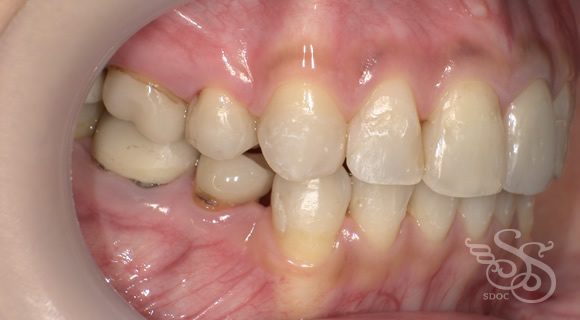

修復物が多い方の矯正

右側:術前

左側:術前